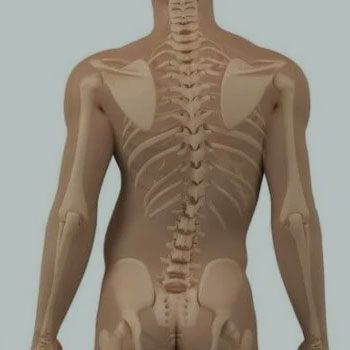

Conhecendo sua coluna

A coluna é formada de 33 vértebras: 24 pré-sacrais, sendo 7 cervicais, 12 torácicas e 5 lombares; pelo sacro composto de 5 vértebras fundidas e pelo cóccix formado de 4 vértebras rudimentares fundidas entre si, sendo...